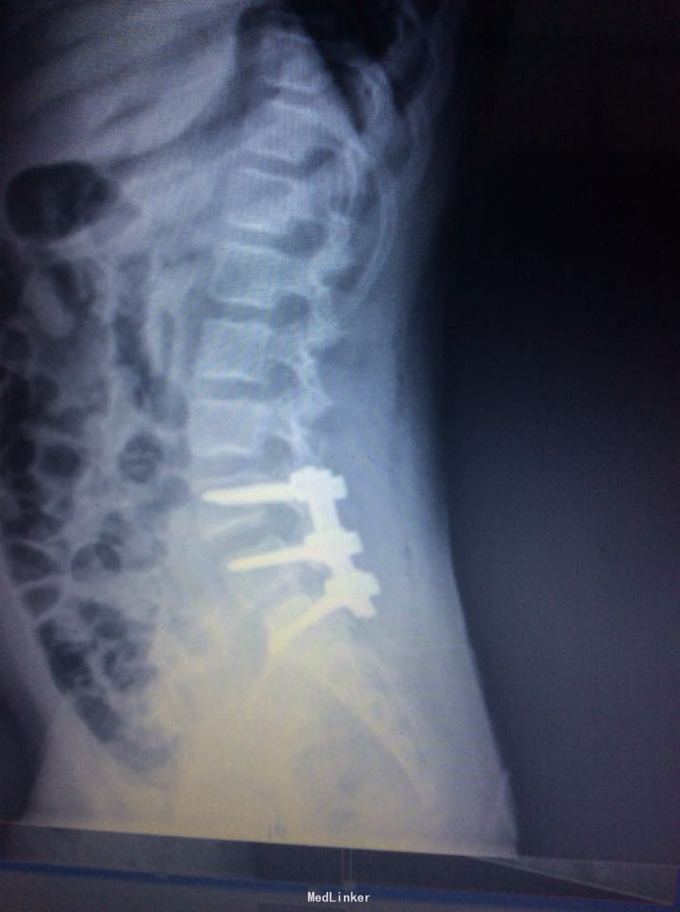

腰椎滑脱

椎体滑脱

9岁,腰痛一年

术前joa 评分17分

腰5椎体滑脱ii度 后路椎弓根钉椎间自体髂骨融合